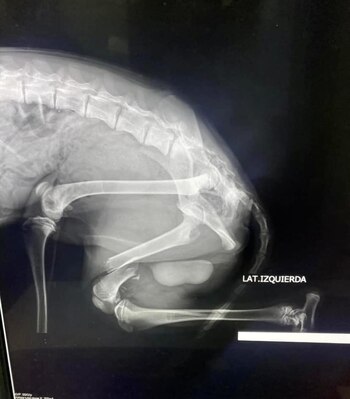

La historia del perro la dio a conocer Caballero el 19 de julio en una serie de publicaciones en su cuenta de Facebook. La rescatista informó a sus seguidores que recientemente había rescatado al cachorro que sufría una fractura transversa de fémur.

Para que tuviera una mejor calidad de vida, Simba necesitaba de una placa con tornillos o fijadores esqueléticos externos. Si todo salía bien, Caballero informó que su cirugía estaba prevista para el lunes 22 de julio a las 14:00 horas.

“Ya lo veremos correr en sus cuatro paticas. Sí se puede, en la unión está la fuerza”, concluyó la rescatista, quien adjuntó una serie de fotografías en su publicación de Facebook, en las cuales se observa el dispositivo que le fue colocado Simba en su pata para que se recupere de su fractura.